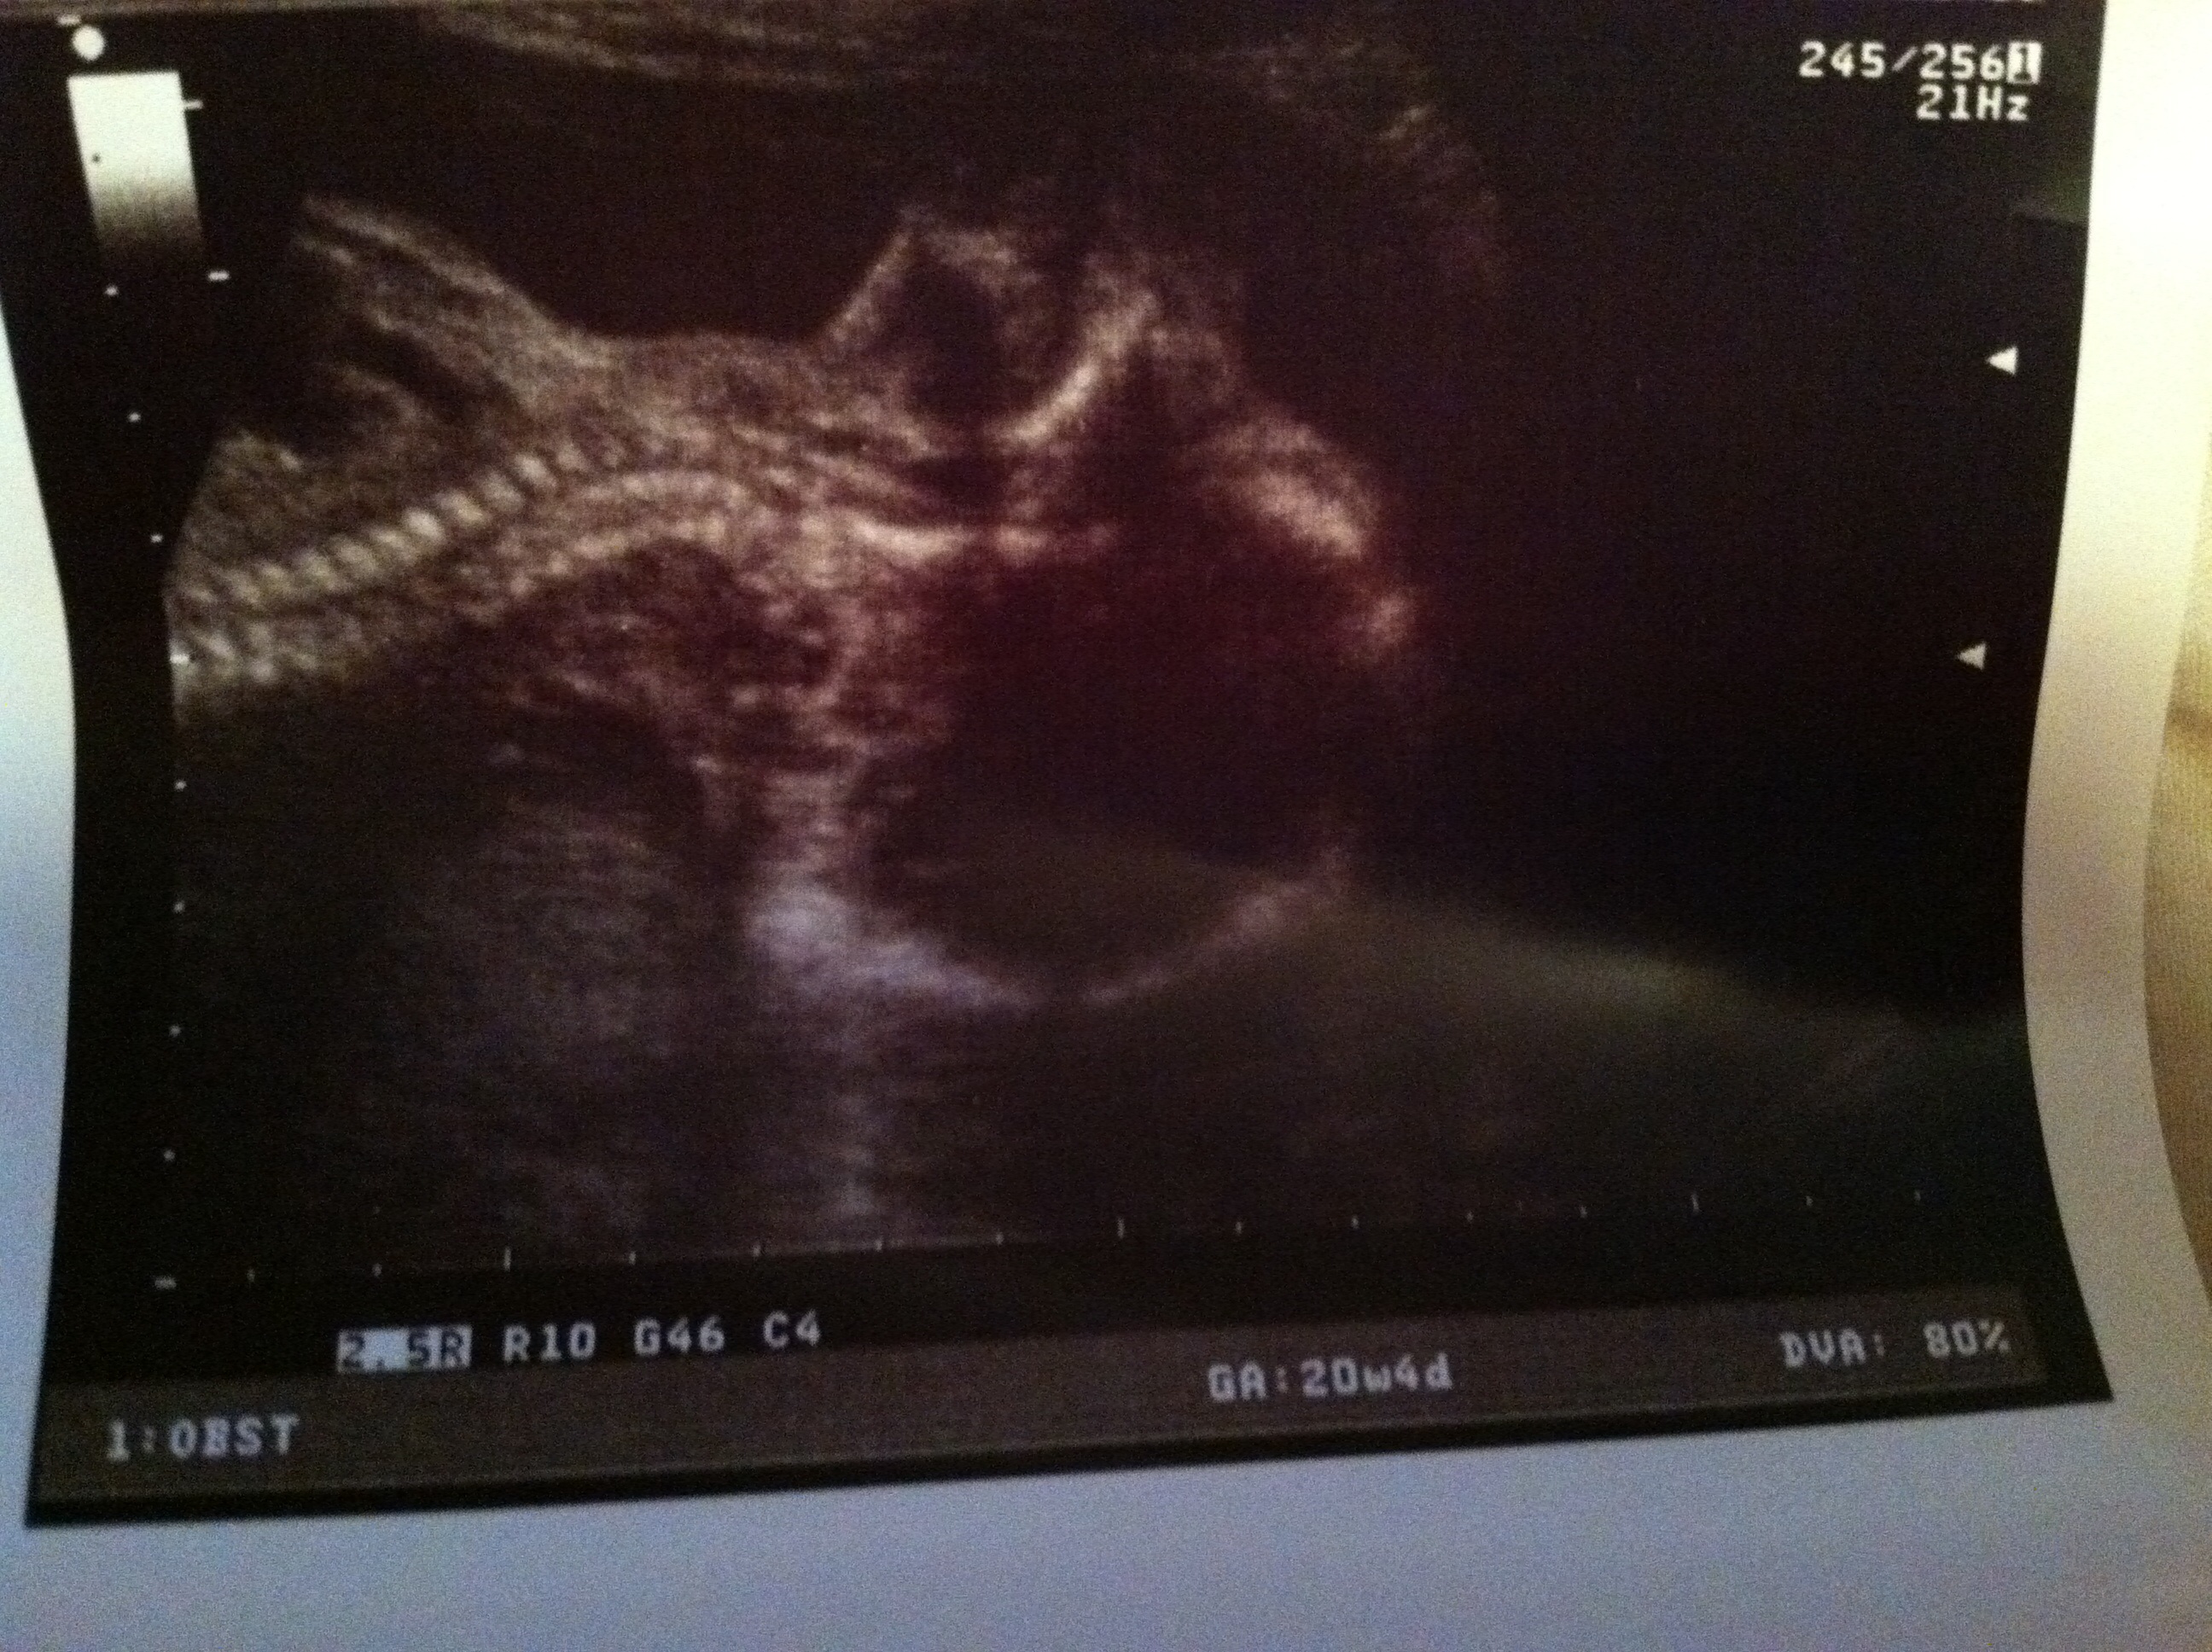

Anatomy scan was perfect! I have myself a very healthy baby boy. At 20 w and 4 days, he already weighs 1 pound 15 oz! His daddy is tall and built and so are his brothers. Little boy was playing with himself during the US.... Oh the joys. My placenta is low but they said not to worry!

His butt was up and face was down pretty much the whole time. This is a picture of his head tilted back;)

Baby "H" due November 7